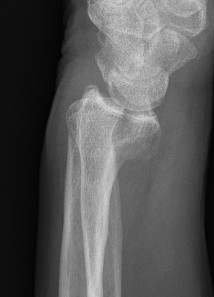

Distal radius fracture with shortening and dorsal tilt

Articular incongruency > 2 mm

Sigmoid notch disruption and DRUJ instability